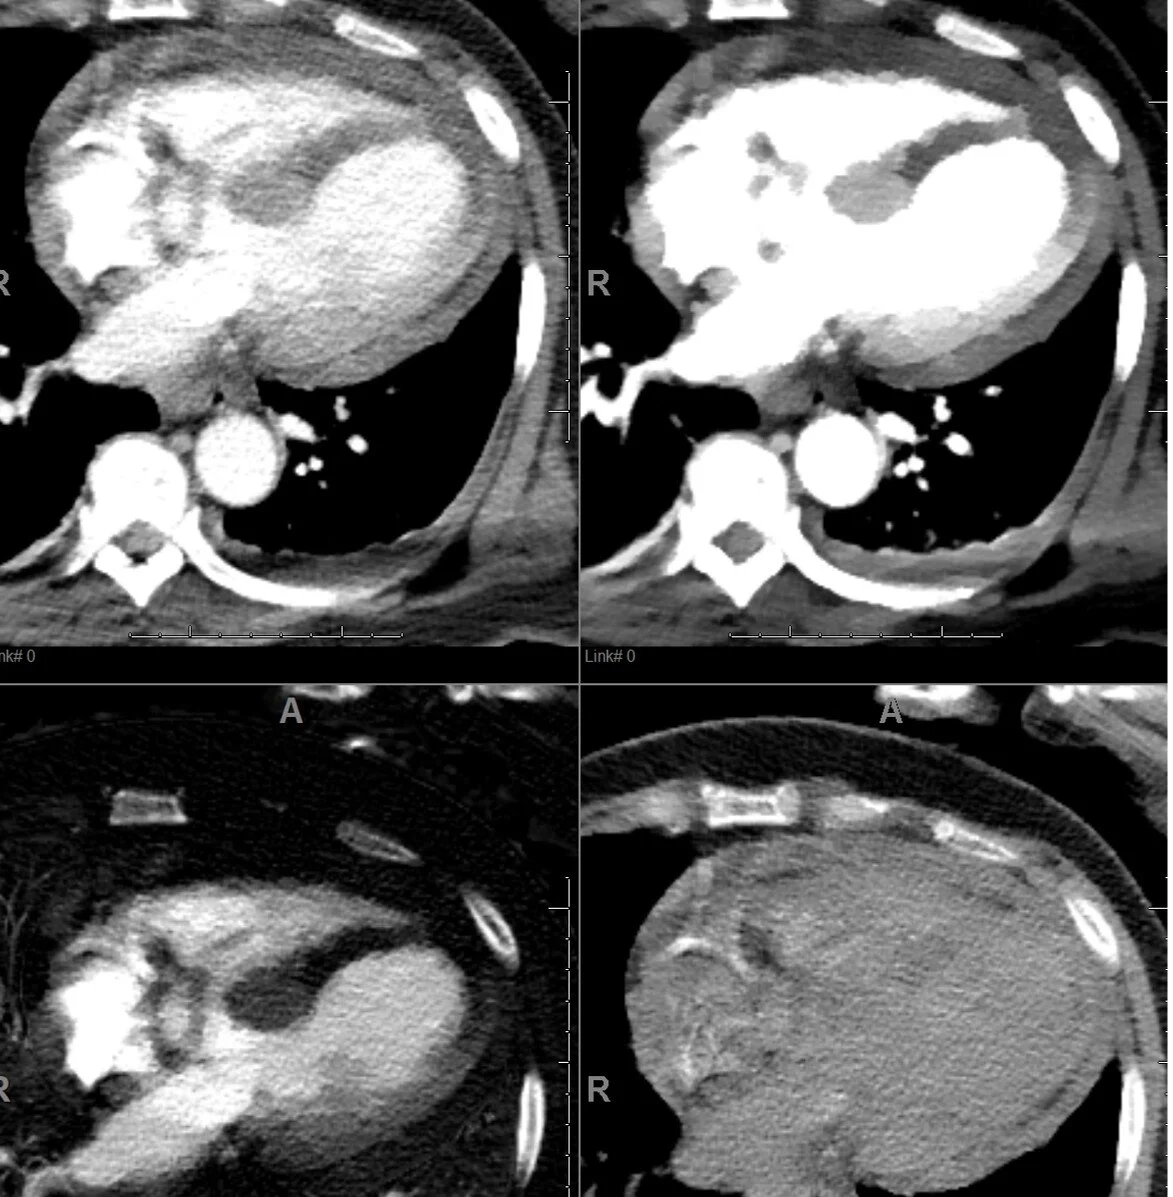

The next day she had abdominal pain and a CT scan of the abdomen and pelvis was performed. There was no acute finding in the abdomen, but the cuts through the lower chest showed interesting findings in the LV. On 40 keV monoE and iodine map, there is a large perfusion defect in the LV corresponding to the LAD territory. This is better seen on short-axis view. On spectral CT, this is a slam dunk, while on routine CT it would be quite a stretch to make this call.

PACS screengrab: Large hypoperfusion in LAD territory best seen on iodine map (left lower image) and 40 keV (right upper image).This is routine where I work: Spectral recons are sent to PACS, and do not need a special system to review.

PACS screengrab: Large hypoperfusion in LAD territory best seen on iodine map (left lower image) and 40 keV (right upper image).

Conventional CT: short axis. You might call the perfusion defect, if you were lucky and having a good day.

40 keV monoE: Impossible to miss

Iodine map